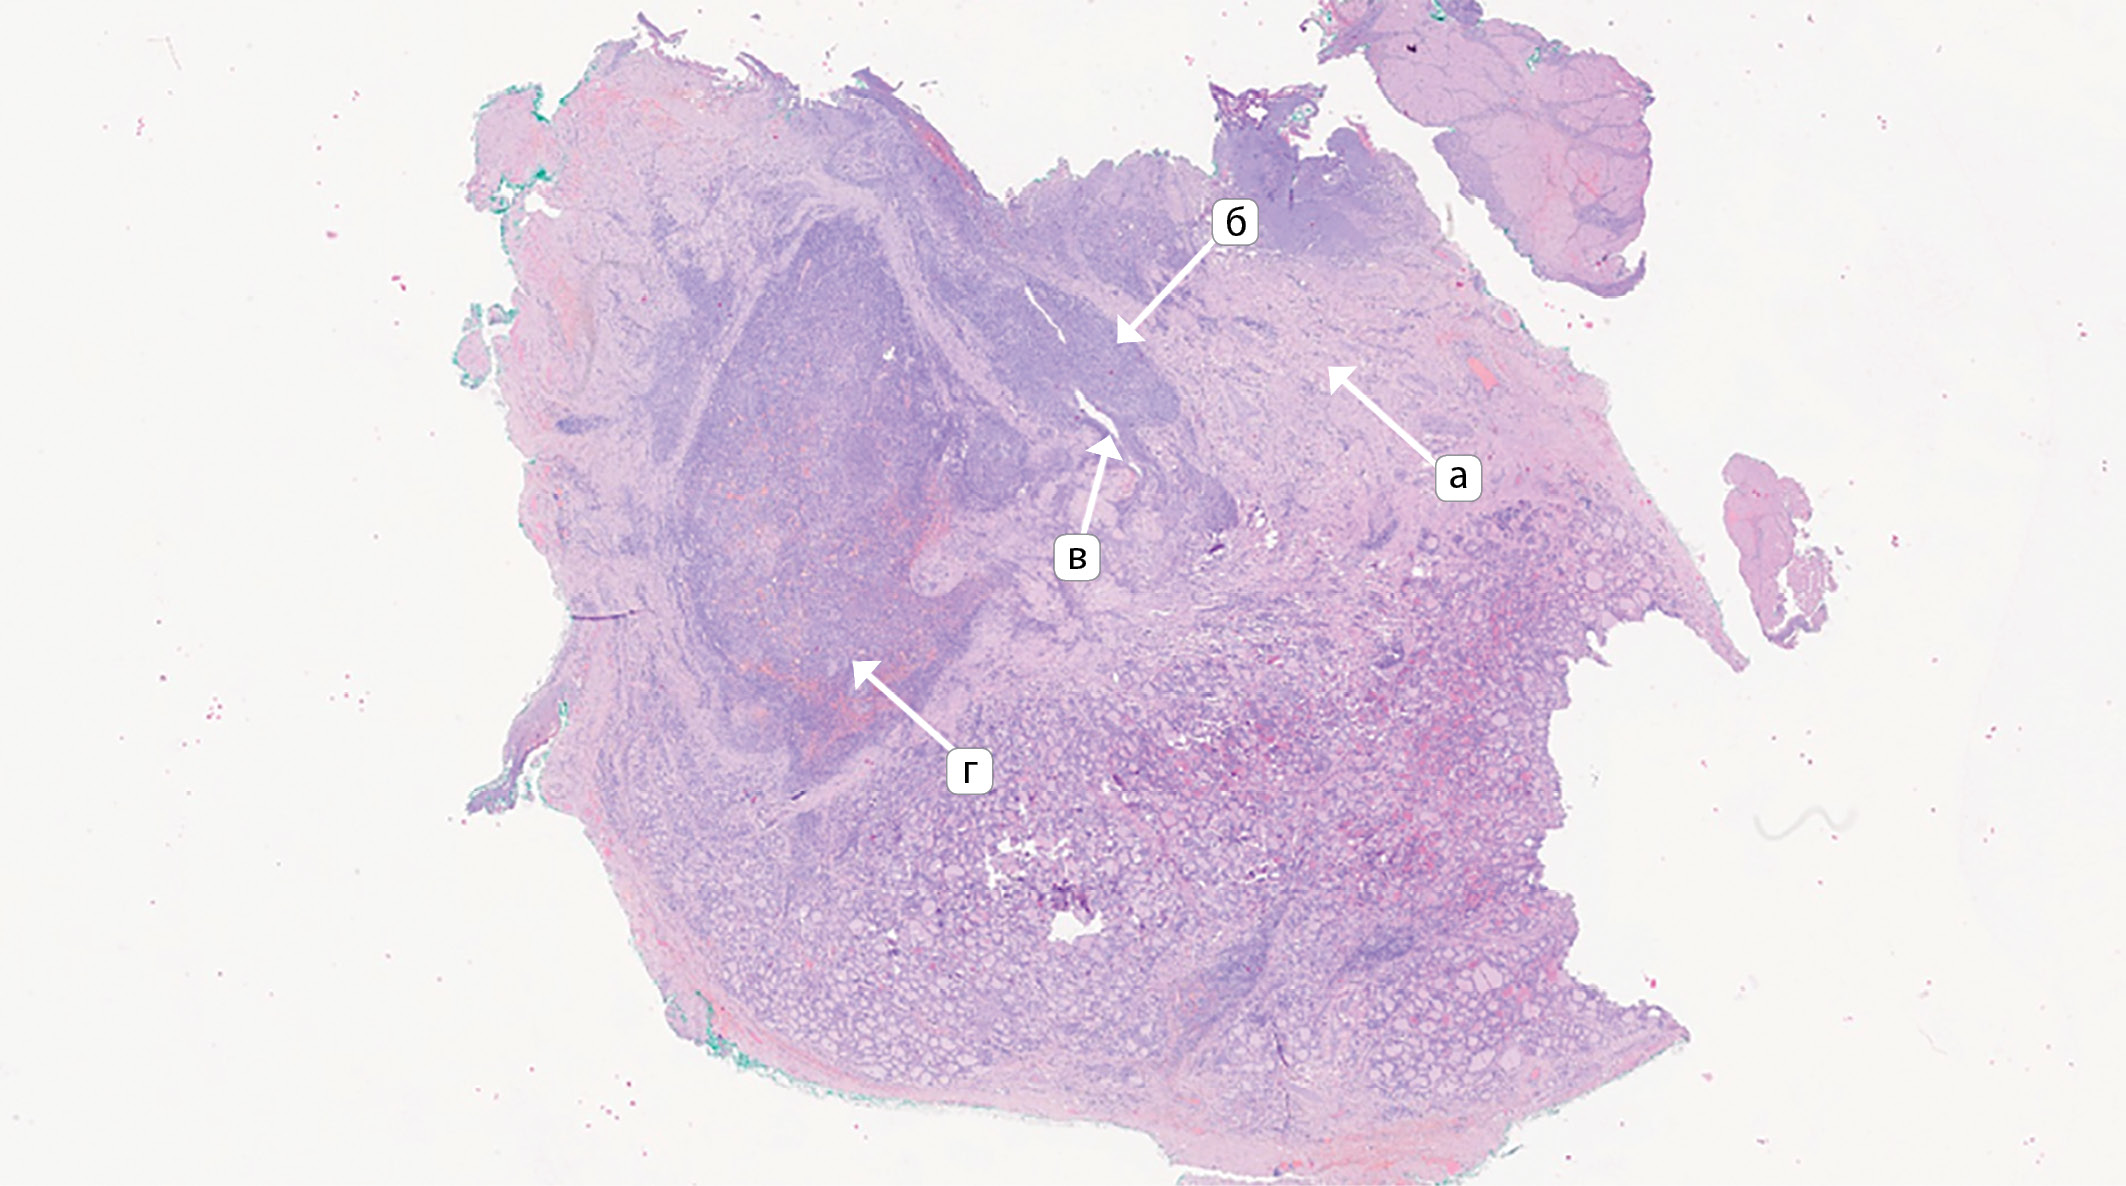

По данным УЗ-исследования ЩЖ, в верхней трети левой доли визуализировалось образование размерами 1,6х1,0х0,9 см с нечеткими контурами, смешанной структуры, преимущественно пониженной эхогенности с умеренным кровотоком по периферии и гиперэхогенными включениями от 0,1 до 0,5 см, EU-TIRADS 5 (рис. 1), объем ЩЖ составлял 3,4 см³. По ходу сосудистых пучков определялись множественные лимфатические узлы диаметром до 0,6 см без видимых изменений.

Рисунок 1. Узел в левой доле щитовидной железы (обведен)

с гиперэхогенными включениями от 0,1 до 0,5 см (указаны стрелками).

Figure 1. Nodule in the left lobe of the thyroid gland (circled)

with hyperechoic inclusions from 0.1 to 0.5 cm (indicated by arrows).